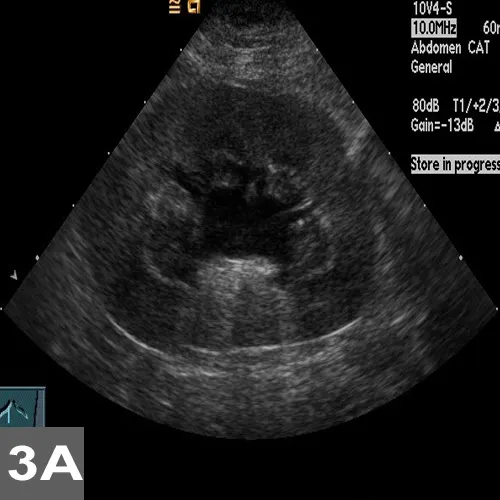

• For complicated UTI, radiography and ultrasonography are indicated for assessment of uroliths, pyelonephritis (Figure 3), prostatitis, adrenomegaly, or other complicating factors. Contrast studies or cystoscopy may be indicated to investigate anatomic defects.

Figure 3. Longitudinal (A) and transverse (B) renal ultrasound images of an 8-year-old female domestic shorthaired cat with pyelonephritis. These images show dilation of the renal pelvis, which is characteristic of pyelonephritis.